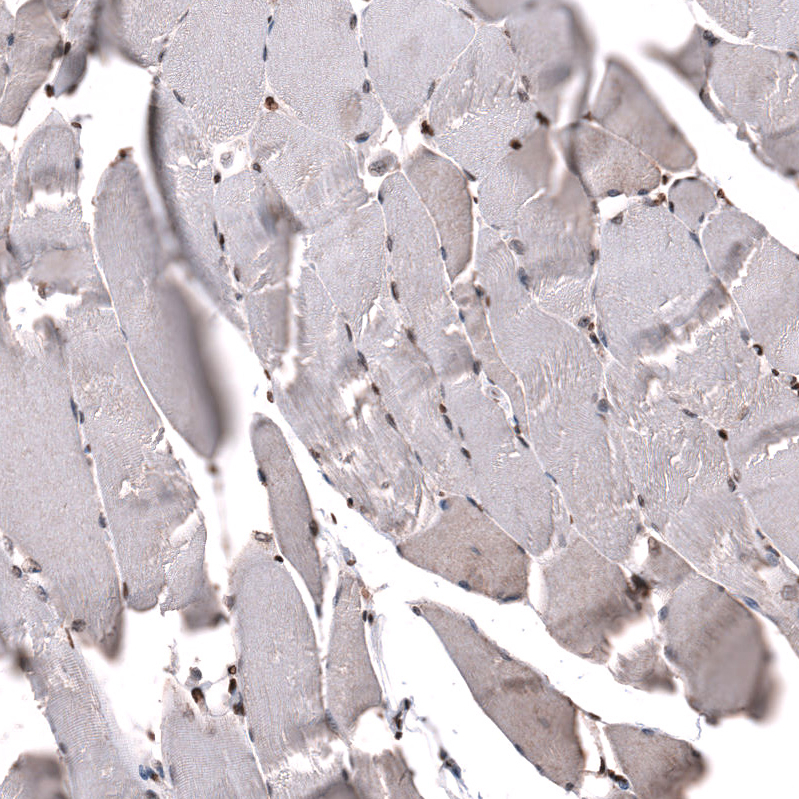

Immunohistochemical staining of human pancreas shows strong nuclear positivity in exocrine glandular cells and endocrine glandular cells.